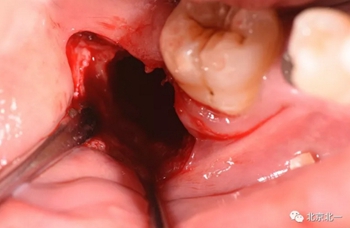

截冠:有絲分裂至關(guān)重要。 保證微創(chuàng)下拔除智齒。

有絲分裂拔牙技術(shù)展示

北一種植王明老師總結(jié):本病例難點(diǎn)在于設(shè)計(jì)多學(xué)科治療。 治療周期拉長(zhǎng), 患者智齒低位, 拔除困難, 容易造成神經(jīng)麻木。 必須由經(jīng)驗(yàn)醫(yī)師主刀。 北一微創(chuàng)拔牙理念主張將牙齒進(jìn)行有絲分裂, 進(jìn)行智齒粉碎。 對(duì)工具要求較高。 較少患者痛苦。